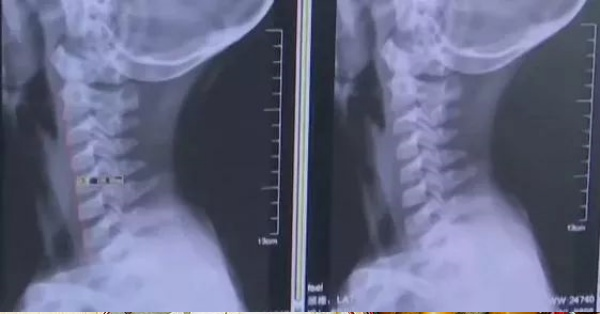

Vài ngày trước, cậu bé cảm thấy đau đầu, đau cổ cổ và chóng mặt.Sau khi mẹ cậu phát hiện ra, đã bảo cậu không được chơi game trên điện thoại di động nữa, điều này khiến cậu bé rất sợ hãi. Sau đó, mặc dù các triệu chứng khó chịu vẫn còn, cậu bé vẫn lén lút cầm điện thoại chơi game, nói dối mẹ rằng mình không còn dùng điện thoại nữa. Tuy nhiên, hai tuần sau, các triệu chứng ngày càng nghiêm trọng và đã đến mức không thể chịu đựng nổi, bé trai 14 tuổi ói với mẹ về sự khó chịu của mình. Người mẹ vội vàng đưa con đến bệnh viện để điều trị. Chụp X-quang cột sống cổ cho thấy: đốt sống cổ có độ cong sinh lý bất thường, thoái hóa đốt sống cổ. Sau khi biết về tình hình của nam sinh, bác sĩ đã nói với cậu bé rằng hãy tránh cúi đầu trong một thời gian dài, nếu không thì cột sống càng ngày càng thoái hóa đến mức không thể chữa trị được.